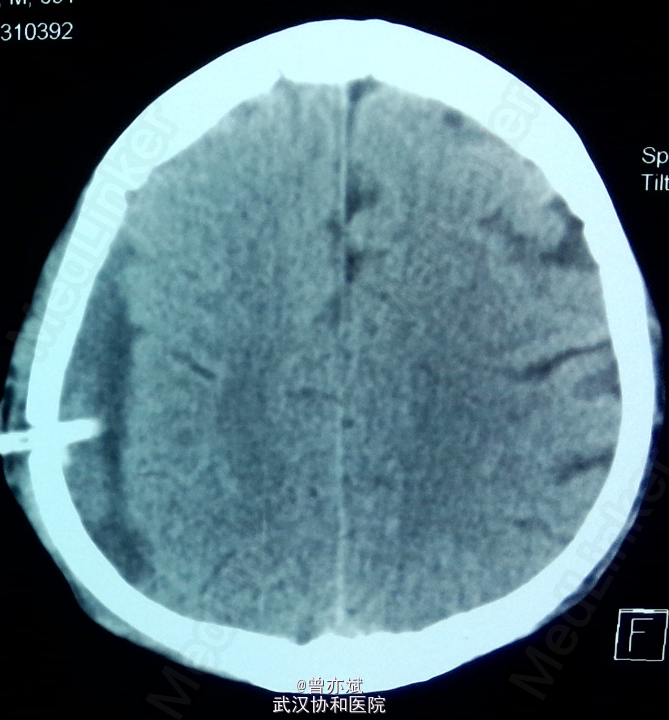

5天后的CT如下:血肿较前稍减少,密度稍减低 摔倒后当时无明显的症状,之后出现慢性硬膜下血肿,特别是在老年人中更易出现,摔倒后弱头部着地,应行CT检查。